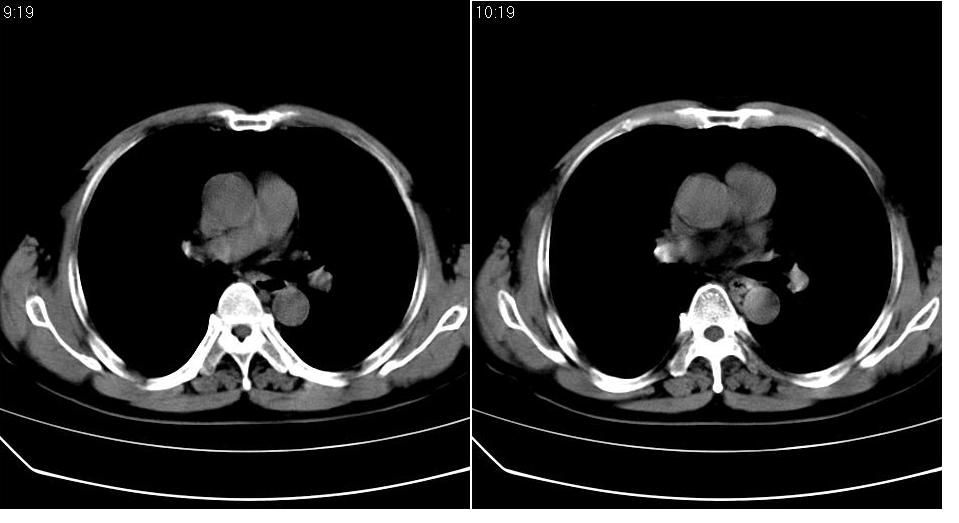

男 60岁,咳嗽,喀痰,胸闷,有吸烟史,正常图片未上传,请谅解。

左肺肿块有分叶、有毛刺,符合周围型肺癌。

分叶状肿块,有毛刺,有晕,有粗纹理直通肺门,支持考虑周围型肺癌